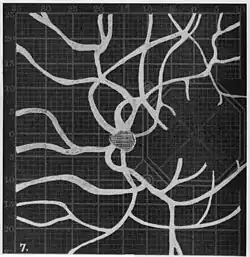

Angioscotomas were first discovered and mapped out by John Norris Evans (1891-02-28--1953-04-08)[2] in 1926, who coined the term angioscotometry to describe the painstaking charting of the scotoma of the retinal blood vessels by manual perimetry. He seated each subject in a seat in a dark setting, and tested whether they could see a tiny bright test object placed at various locations.[3] Using a 1.5 mm white disk, Evans reported intricate branch‑like scotomas that mirrored the arteries and veins emerging from the optic disc, with a full map requiring up to 2 hours to complete. He plotted this for subjects under various conditions, such as while holding breath, with glaucoma, etc. A year later, he confirmed that only short stump‑like scotomas had been noticed previously, some further data plotted with a smaller 1 mm stimuli, and under varying conditions on the subject.[4] He published a monograph on this in 1938 in which he described its use in assisting diagnosis of various conditions, such as retinal edema, glaucoma, optic neuritis, etc.[5]

Using eccentric fixation, the more nasal parts of the angioscotoma can be plotted. -

Widening of angioscotoma under various conditions (holding head lower than trunk; holding the breath; making digital pressure on the same eye; (a vein) on opposite eye; (an artery) on opposite eye).